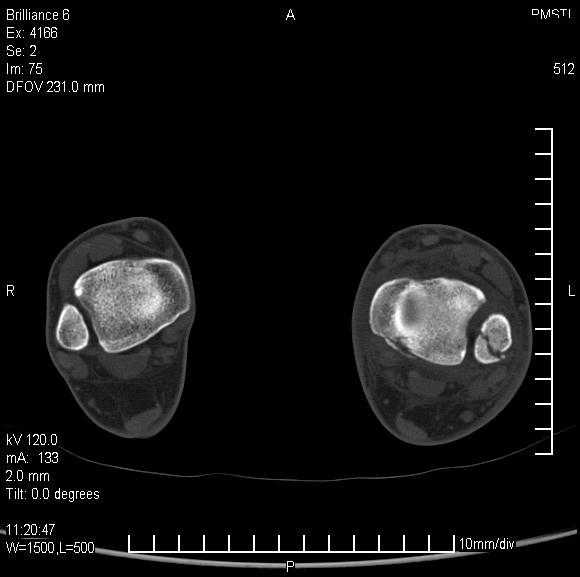

Уважаемые коллеги!Помогите, пожалуйста, советом! Пациентка 14 лет.

Двухлодыжечный

перелом с (как нам кажется) повреждением межберцового синдесмоза.

Вопрос один: оперировать или оставить "как есть" в гипсе? Не будет ли в

дальнейшем проблем с суставом. Заранее спасибо.